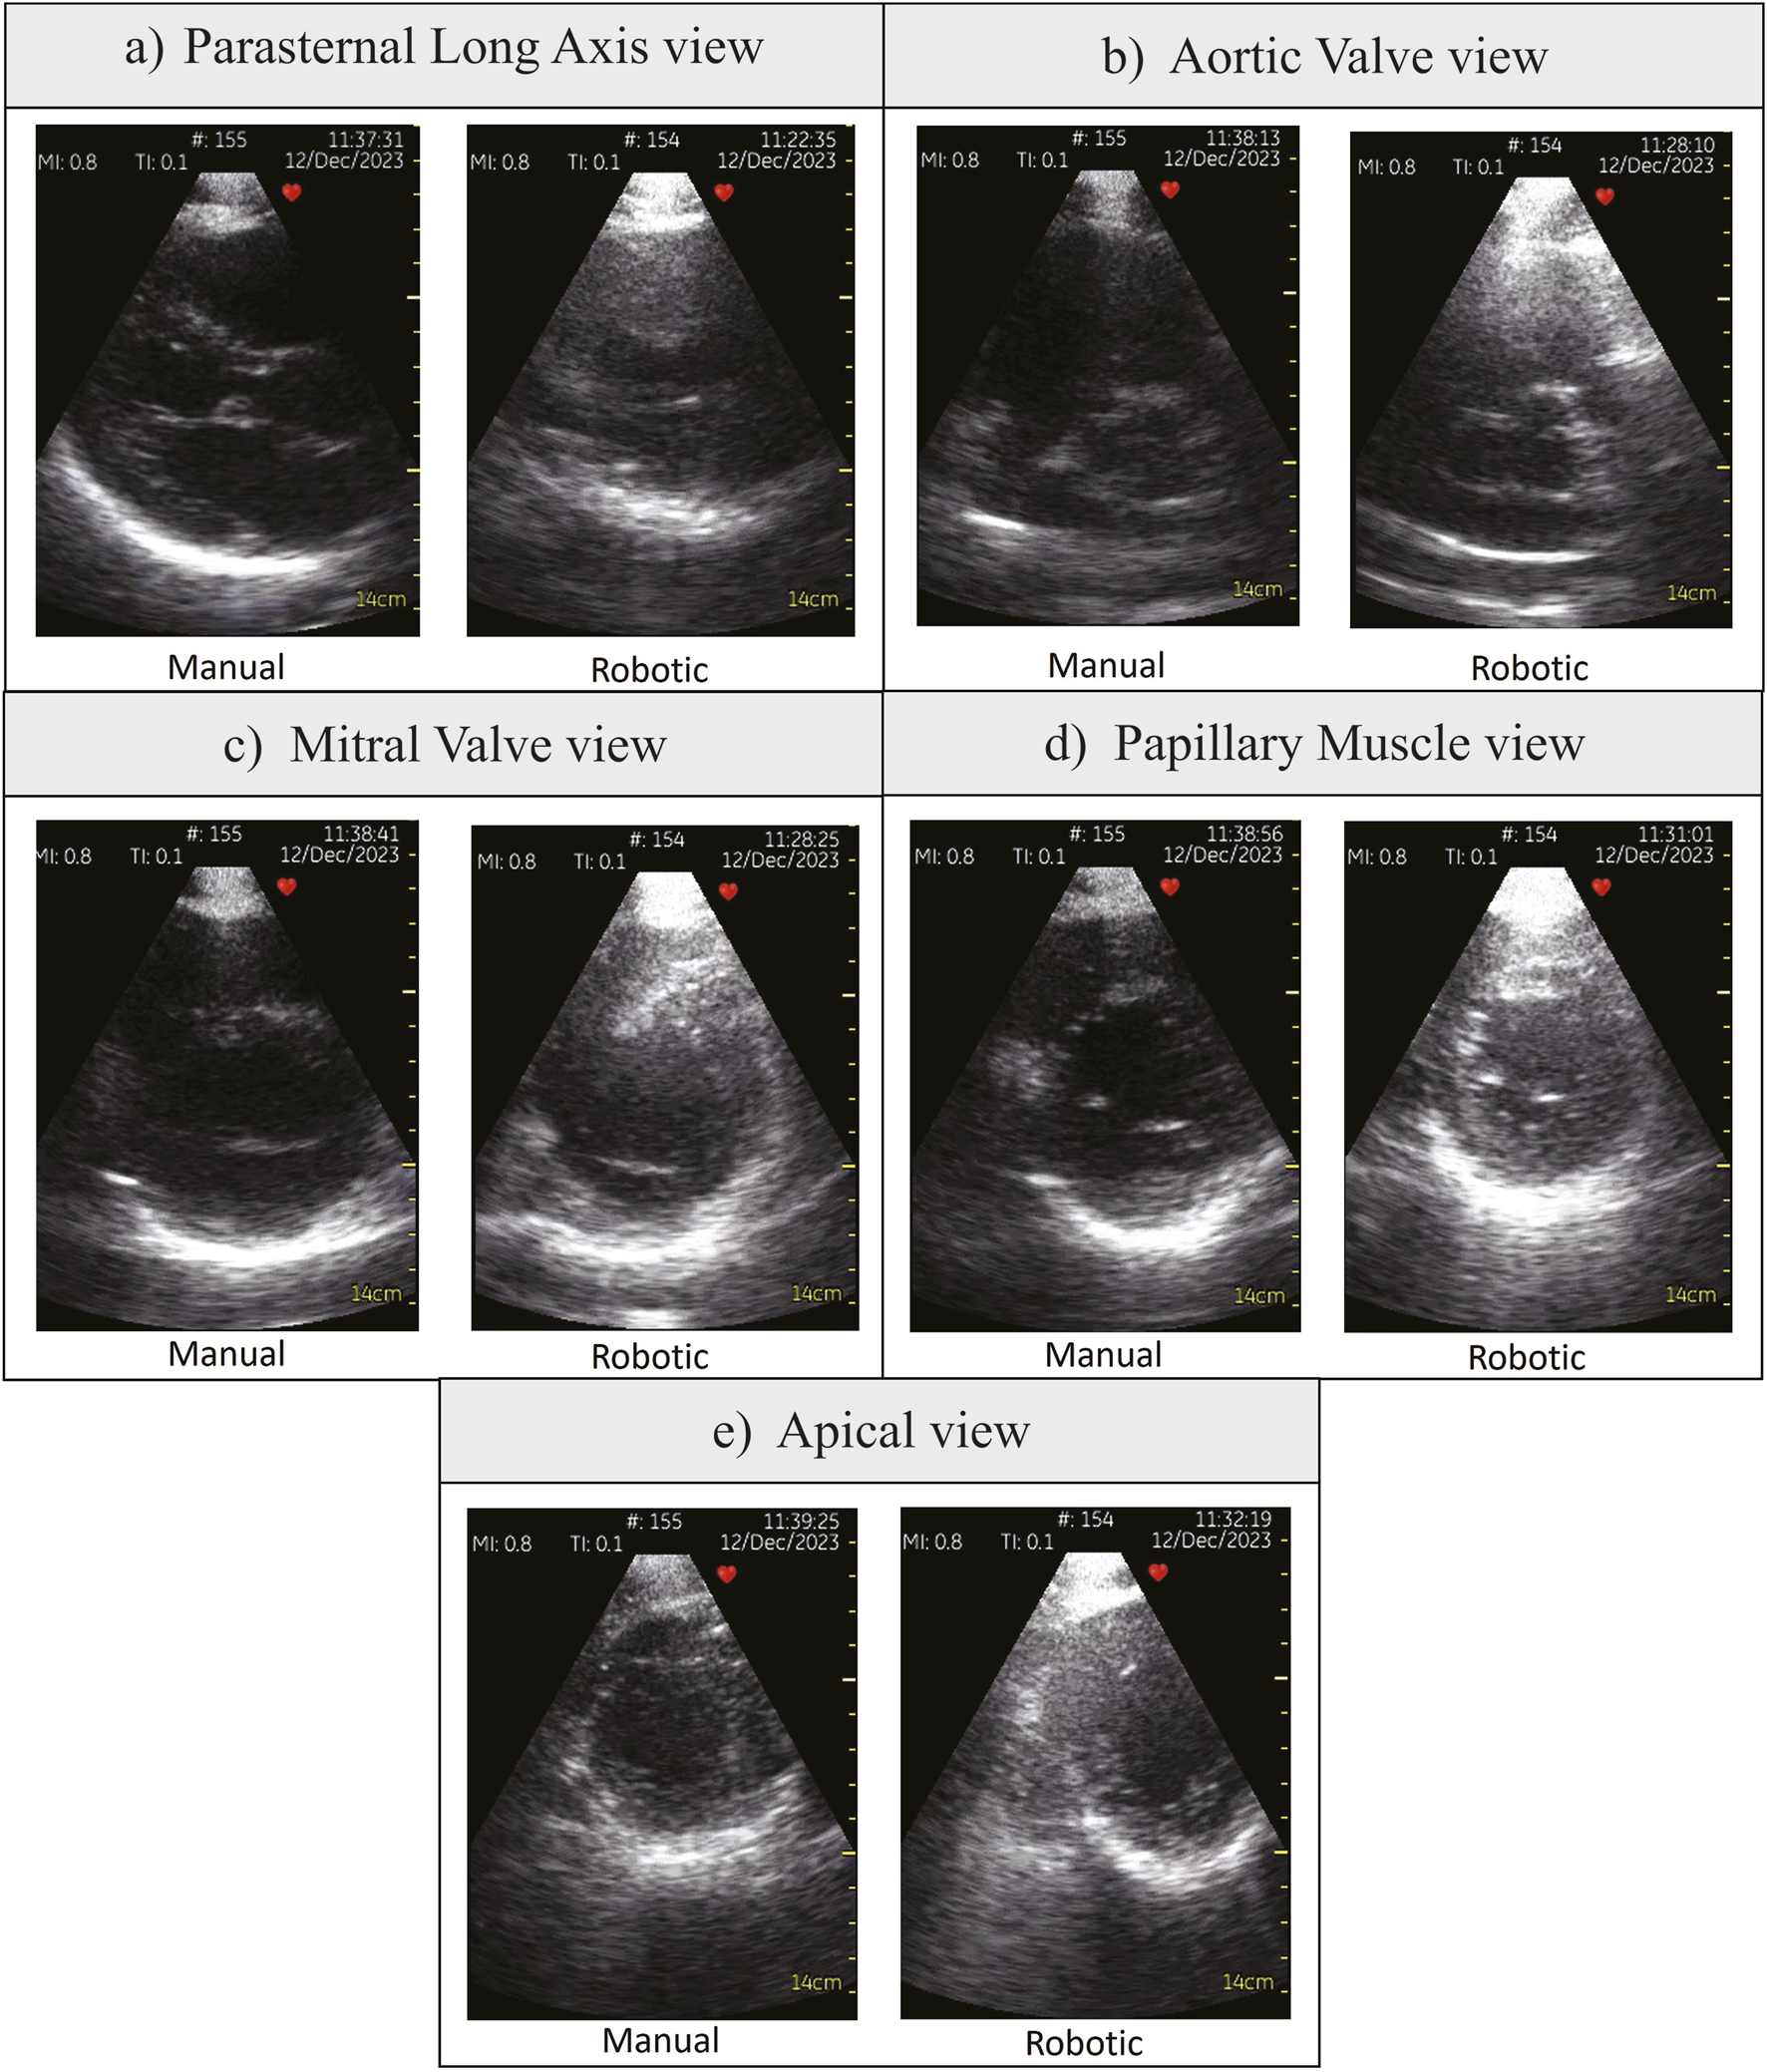

Table 1 shows the statistical analysis comparing all participants’ robotic and manual scanning performance and dividing them into students and doctors groups. Figures 4A, B show the time to the window and the total scanning time of the manual and robotic exams, respectively. The number on top of the bar chart is a ratio of the obtained views out of the five required views. All the required views were obtained by all the operators both with the robot and manually. Figure 5 presents examples of the five views obtained with the robot and manually from participant P4, a doctor.

Figure 5. Various parasternal views obtained by participant P4, a doctor. (A) Parasternal Long Axis view, (B) Aortic Valve view, (C) Mitral Valve view, (D) Papillary Muscle view, (E) Apical view.

Our primary aim with the prone position design is to build a robot with reliable movement and safety experience in a closed-loop control. First, we will discuss the robot safety strategy in the image acquisition context. Generally, the patient felt comfortable during the scanning as the patient was able to fall asleep during a few of the trials. Sometimes, uncomfortable scanning forces did happen, so the patient just said it out loud and the medical personnel would lower the robot position to decrease its upward thrust. This is possible due to joystick button controlled upward movement, so the movement bandwidth is limited to the frequency of button stroke. There was never any case in which the robot disengaged due to the stepper motors threshold achieved. All medical personnel could obtain all the required views using the robot, with the doctors’ image scores stayed constant compared to the manual scan (Figure 7). Solvin et al. (2023) also performed teleoperated echo trials using industrial robot UR5 with the control algorithm described in Mathiassen et al. (2016). Their safety strategy was to limit the contact force to 5 N and retract the robot if this limit is reached. However, during their experiments, the force limit could be incidentally reached due to the jittery probe movement Solvin et al. (2023). If it happened, the robot would withdraw and the operator would need to repeat the image acquisition movement sequences, which makes fine probe adjustment more tedious. As a result, the robotic exam image scores were 1.6 on average in contrast to the manual scan score of 2.5 in 0–3 Likert scale (Figure 4 in Solvin et al. (2023)). In rigid robots, such concurrent adaptive force and orientation control could be attained using hierarchical approach Santos and Cortesão (2018), which resulted in accurate orientation tracking. However, the setup needed force sensing, depth camera, and online stiffness estimation which has significant computational cost. Compared to a rigid robot, a compliant end-effector has small force gradation due to its low stiffness, so it does not need a precise force tracking algorithm with high bandwidth. Because the patient can tolerate force increment during tilting, we could implement a step-wise increment of actuator bending without force sensing. Using this approach, the doctors could obtain images from various view planes with similar quality to the manual scan (Figure 5).